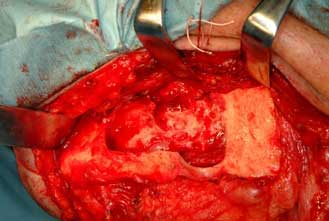

歯原性腫瘍で発生頻度の高いものは歯牙腫とエナメル上皮腫で、約90%を占めます。治療として

は腫瘍の外科的切除が必要です。前記のエナメル上皮腫のように良性であるが再発しやすい腫瘍

については繰り返し切除手術(反復掻爬術)を行う必要があります。腫瘍が大きくなり、広範囲

にあごの骨が吸収している場合はあごの骨を部分的に離断し、切除することが必要な場合があり

ます。あごの骨を部分的に離断、切除した場合にはチタン製プレートによる固定や骨移植を行い

再建する必要があります。

| エナメル上皮腫切除後(下顎骨) | チタン製プレートによる再建 | |